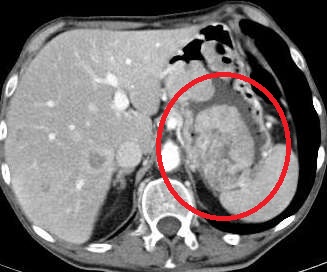

病例2:终末肾患者,肝硬化腹水。腹水穿刺引流后低血压,CT扫描发现活动性出血,造影剂外溢

术后